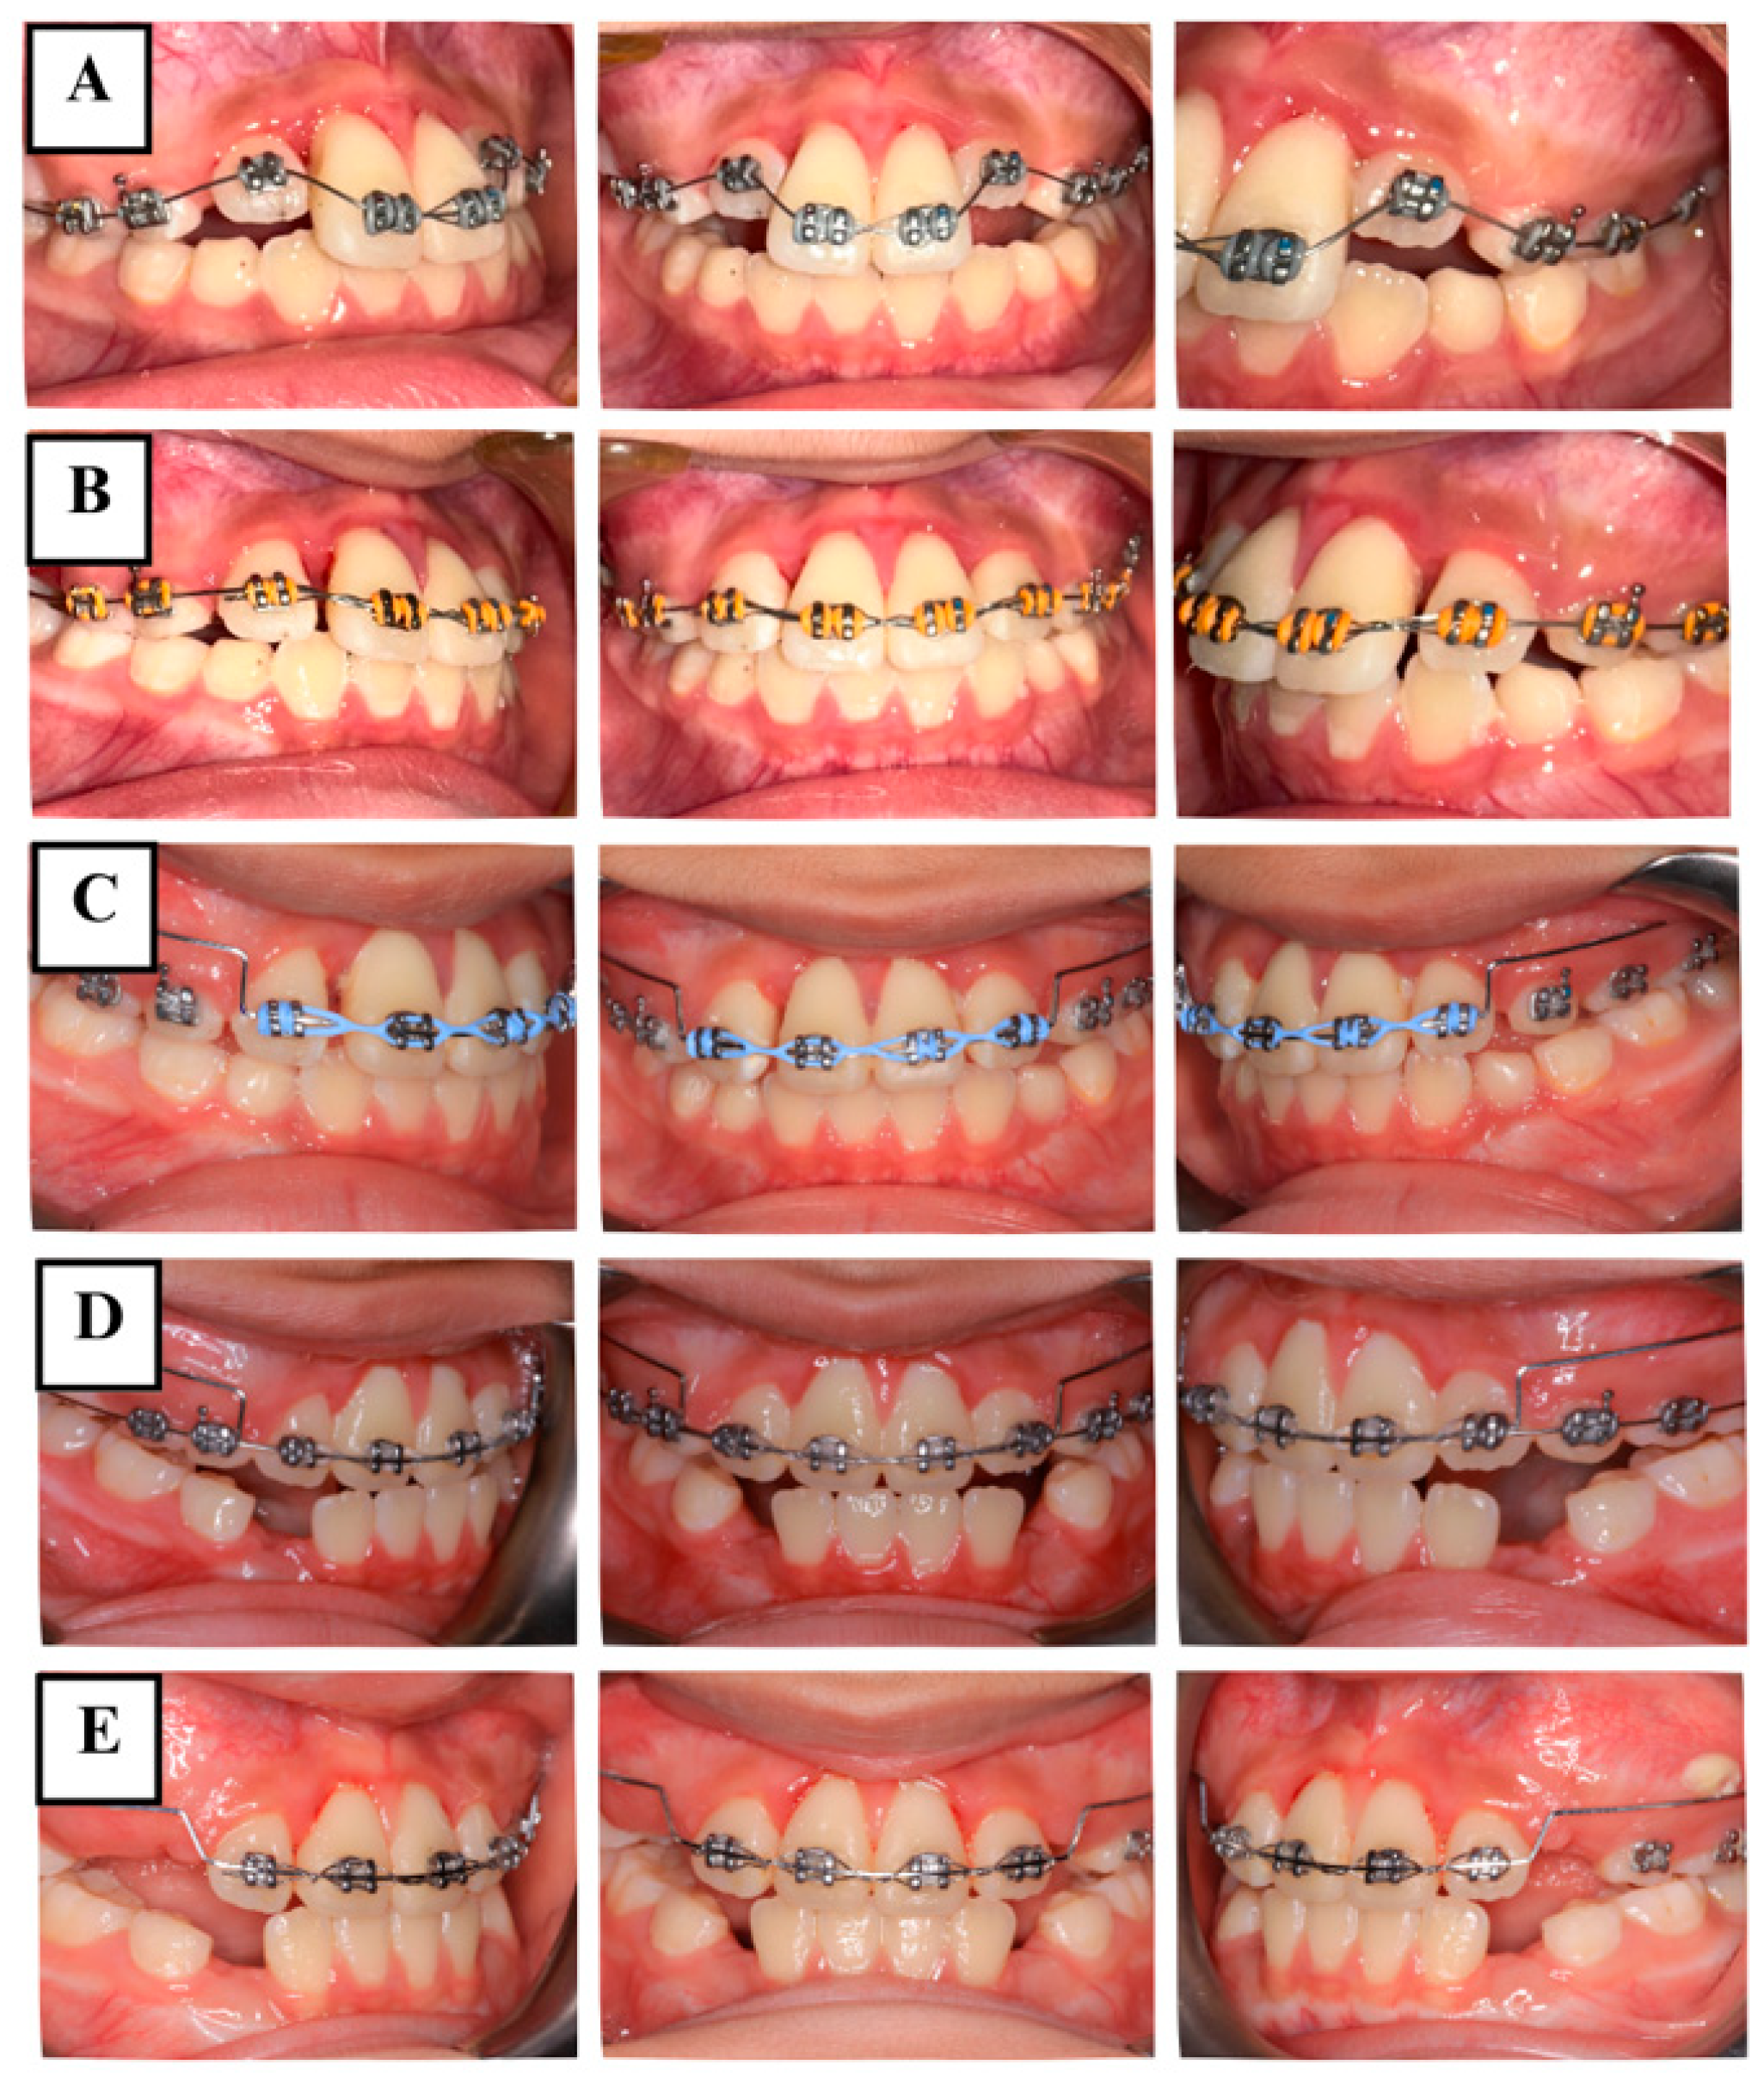

The anterior teeth were initially aligned to allow for more effective tooth movement later (Figure 4A). Once the teeth were properly aligned after 8 weeks (Figure 4B), the coronal fragments of teeth #11 and #21 were then repositioned and stabilized using a utility arch constructed from 0.016 × 0.022-inch blue Elgilol wire (Figure 4C,D). Fourteen months later, teeth #11 and #21 remained clinically asymptomatic. The extrusion of both teeth had been corrected to 0 mm, and mobility was close to normal (Figure 4E). At this time, EPT still showed positive results. Radiographs indicated satisfactory periodontal tissues around both of the fractured fragments and the apical area, without evident radiolucency of apical inflammation or root resorption seen on the CBCT (Figure 5).

Figure 4.

Intraoral photographs during orthodontic treatment. (A) Teeth alignment. (B) at 8 weeks. (C) orthodontic repositioning using the utility arch. (D) at 6 months. (E) at 14 months.